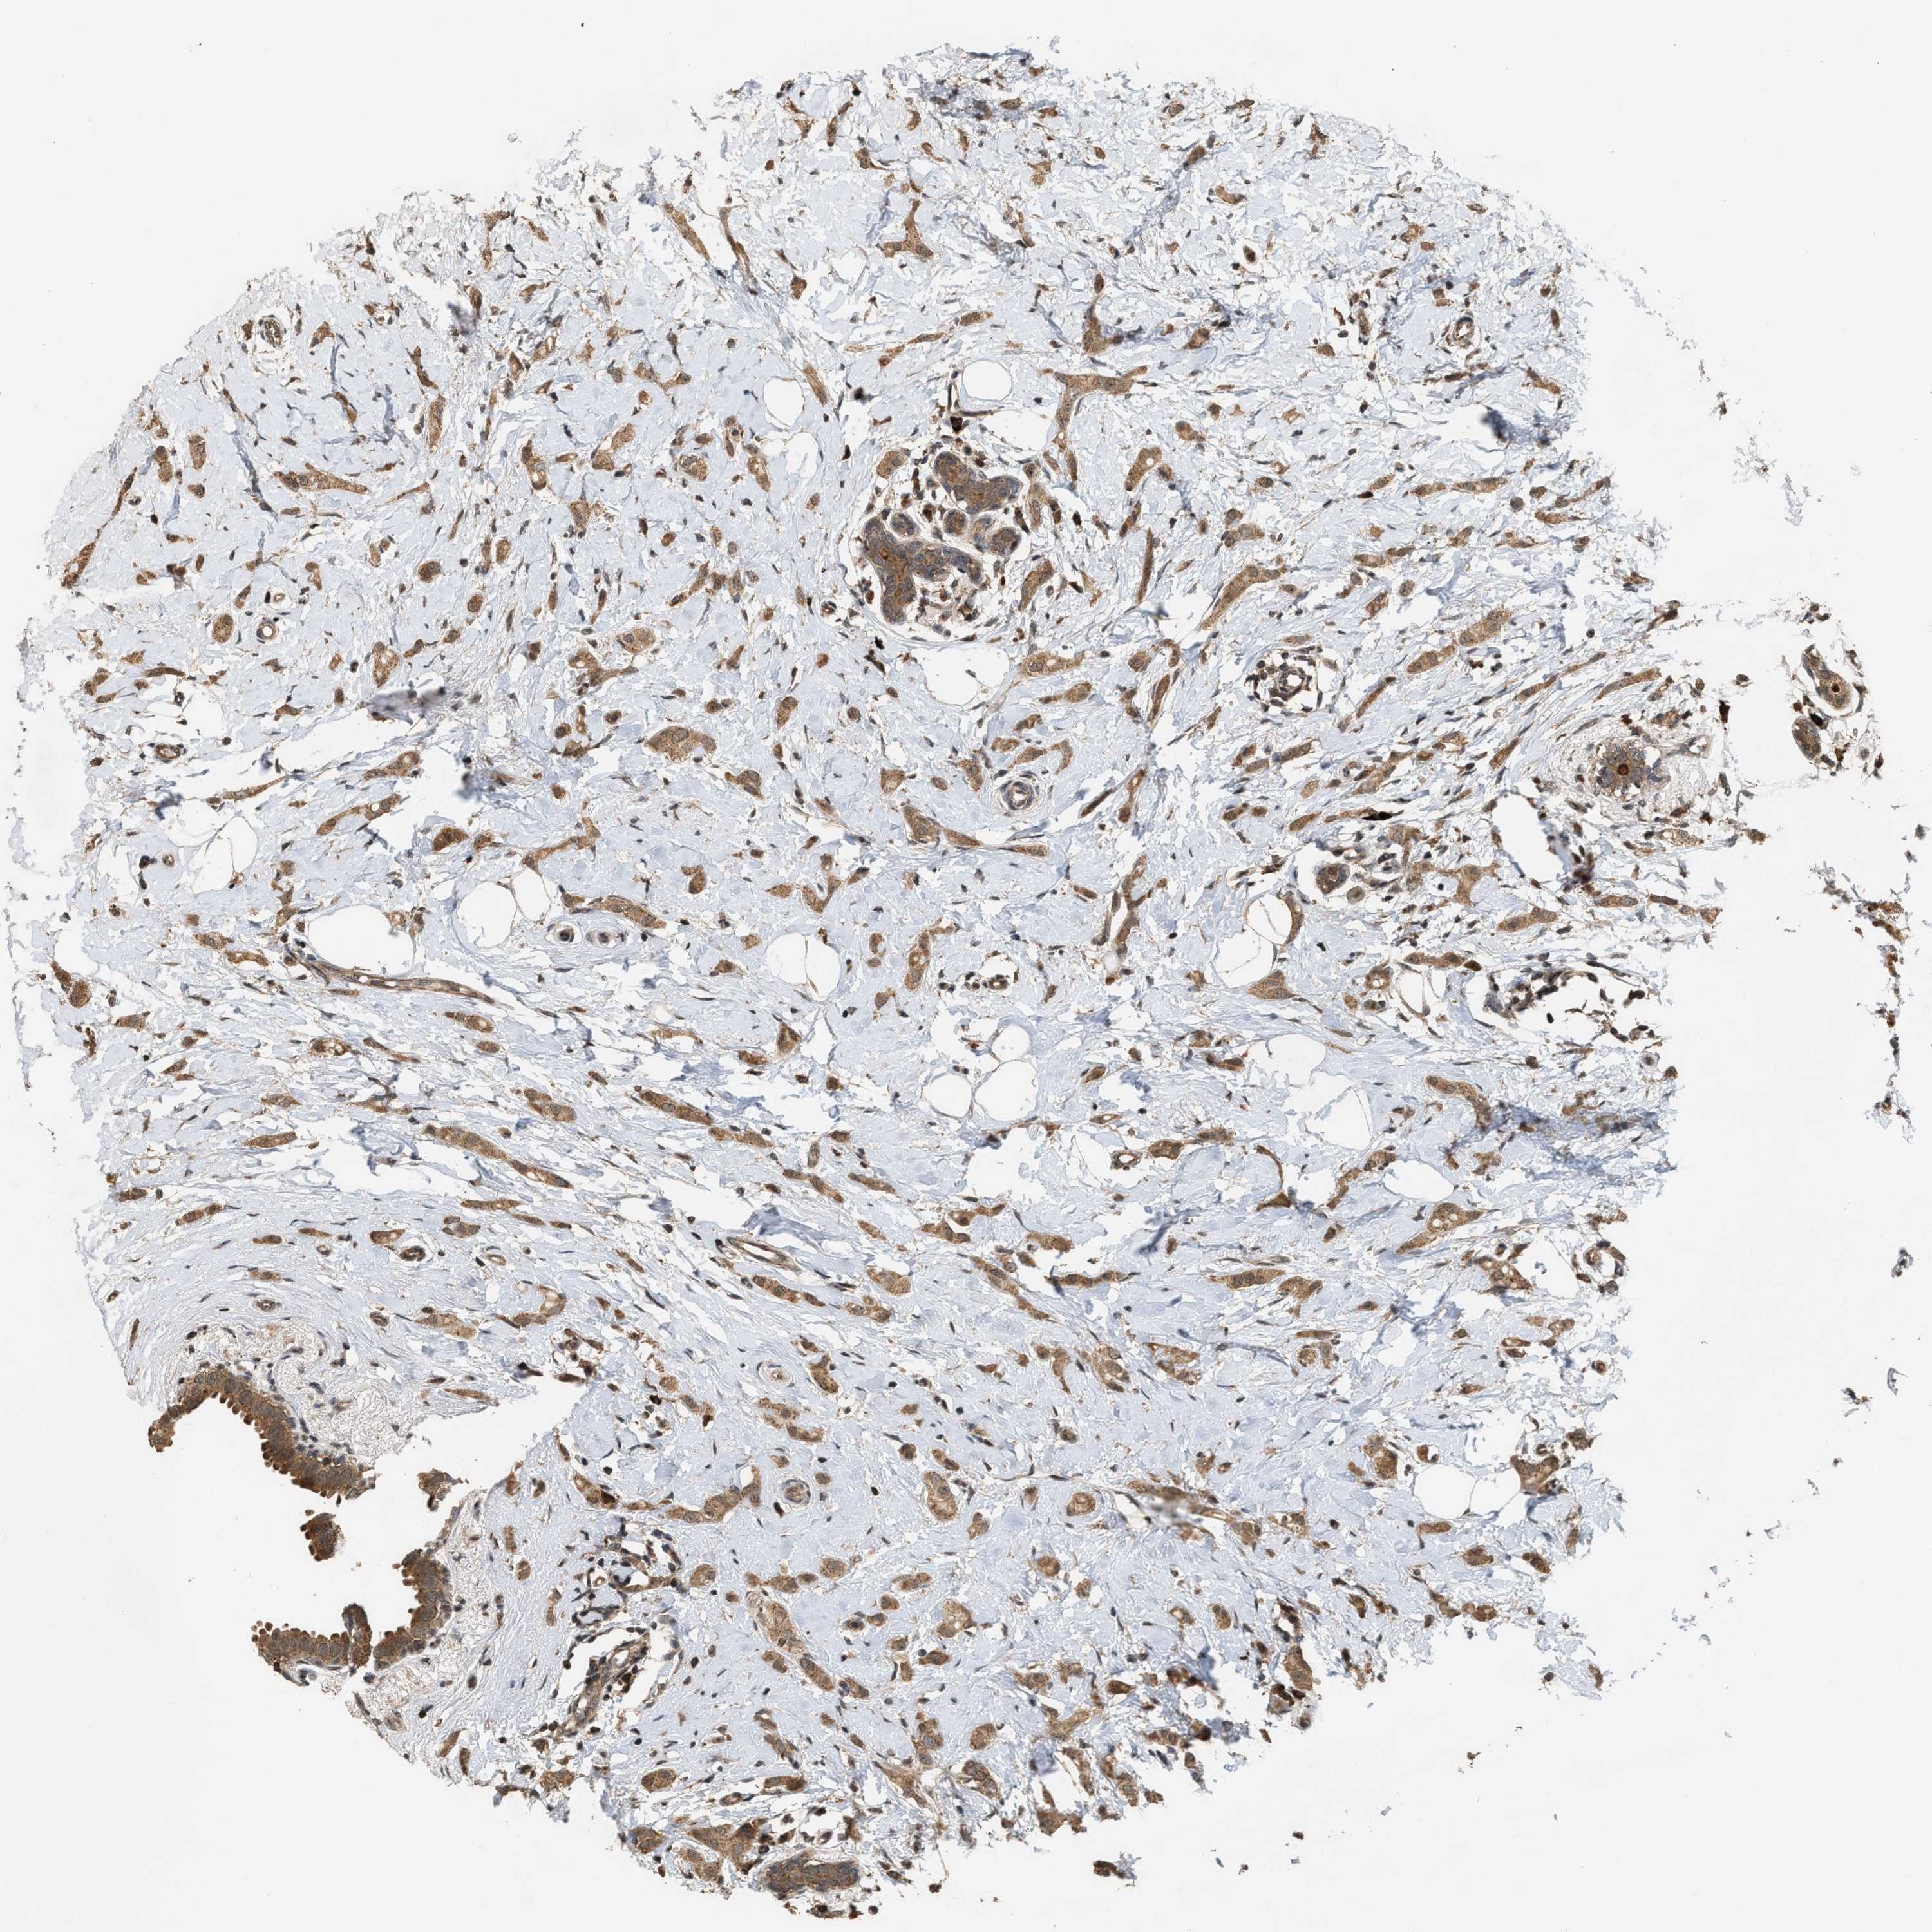

BRCA TCGA BRCA VALIDATION PROTEIN EXPRESSION

ANTIBODIES

AND

VALIDATION